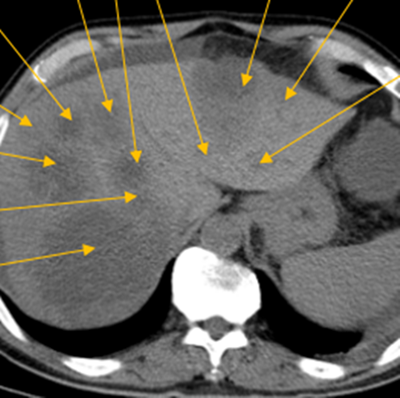

隨后,根據(jù)基因檢測(cè)結(jié)果制定了化療+靶向治療方案。經(jīng)過精準(zhǔn)治療,劉大爺?shù)牟≡畲笮⊙杆倏s小,病灶數(shù)量不斷減少,影像學(xué)評(píng)估已經(jīng)看不見之前那些小的病灶了。

治療前:箭頭處均為轉(zhuǎn)移性腫瘤